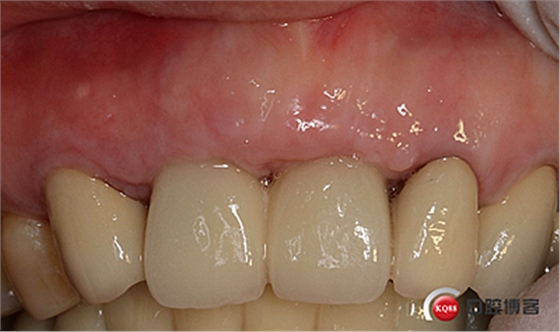

大家看看前后對(duì)比,效果不錯(cuò)。

全瓷冠制作完成,齦乳頭預(yù)留空間不足,修整三角間隙。

戴牙。

戴牙后半年復(fù)查。